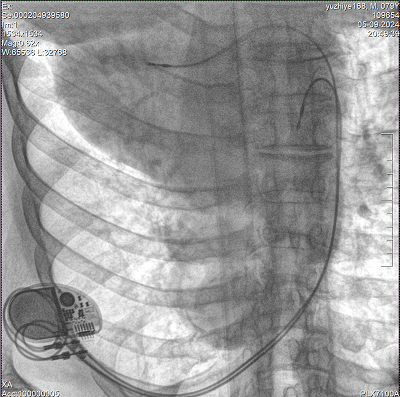

具備血管造影及數(shù)字減影(DSA)、路徑圖(Road-map)、透視、攝影等功能。 廣泛適用于介入科、血管外科、腫瘤科、消化內(nèi)科及骨科等多個臨床科室,典型應(yīng)用包括:TACE(肝腫瘤栓塞與化療灌注術(shù))、心臟起搏器置入術(shù)、四肢動脈造影術(shù)、下肢靜脈濾器置入術(shù)、ERCP(經(jīng)內(nèi)鏡逆行胰膽管造影術(shù))等。

核心DSA軟件可實時生成高清血管影像,結(jié)合路徑圖功能,在手術(shù)中為醫(yī)生提供血管導(dǎo)航。

設(shè)備搭載自主研發(fā)的大功率高壓發(fā)生器、高熱容球管與大尺寸平板探測器,配合先進(jìn)圖像處理算法及高效冷卻循環(huán)系統(tǒng),能夠在長時間手術(shù)過程中持續(xù)輸出高清圖像并保持幀率穩(wěn)定。